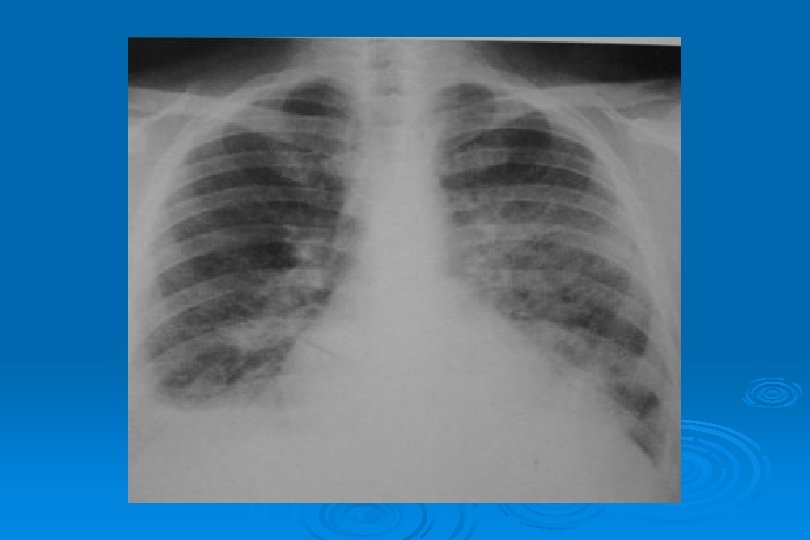

AKUT İNTERSTİSYEL PNÖMONİ Ø Bronş duvarında kalınlaşma Ø İnter ve intralobüler septalarda kalınlaşma sonucu hilustan perifere doğru yayılan retiküler patern Ø Yaygın milier görünüm

LOBÜLER VEYA ASİNER İNFİLTRASYONLAR Sekonder pulmoner lobüllerin opasifikasyonuna bağlı yamalı konsolidasyon görünümü (bronkopulmoner infiltrasyon) Ø Bronş etrafında 1 cm’den küçük asiner nodüller Ø Yaygın asiner nodüller suçiçeği pnömonisi için tipiktir Ø

LOKALİZE VEYA YAYGIN HEMORAJİK ÖDEM Lokal olduğunda radyolojik görünümü segmenter veya lober pnömoniye benzer Ø Yaygın hemorajik ödem akut ve şiddetli viral pnömonide hızla ortaya çıkan bir tablodur Ø Perihiller perifere doğru azalan yaygın alveoler opasiteler görülür Ø Bazen plevral effüzyon olaya eşlik eder Ø İnfluenza virüsü en sık nedendir Ø